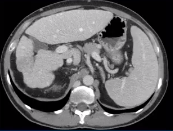

本栏目介绍了几个TACE导致100% HCC 坏死的参考患者。来自同一个中心收集,TACE未导致100% 肝癌病灶坏死(预期或意外)的患者也被讨论,目的是明确100% 肝癌完全坏死的阳性预测因素。

在治疗期间(2003年10月- 2011年1月),采用微球、碘油和2 00 mg卡铂 (mcTACE) 联合进行TACE。

51例 HCC (pT1-T3) 在米兰标准内(65%),在米兰标准之外外(35%)接受126次 (1-6次)cTACE作为肝移植的桥梁,最后一次TACE与肝移植之间的中位时间为145(14-573)天。23例(45.1%)患者TACE周期不完整。在12例(24%)、11例(22%)、18例(35%)和10例(20%)患者中,检测到100%-、99>90%-、90 >50%-和≤50%- HCC坏死。

根据使用的微球的类型和大小,观察到不同的栓子分布模式。肝细胞癌旁肝实质局灶性坏死(14例[28%])和肝细胞癌内微脓肿(13例[26%])是最常见的不良反应。总生存期为0.1->17年。

TACE作为经动脉治疗显示出显著的治愈治疗潜力。完整的TACE周期,优化的栓塞技术(例如,将微球类型与HCC的血管结构相匹配),以及在残余存活的HCC情况下进行密切的TACE影像学随访,应作为移植的积极预测因素进行讨论。100% 肝癌坏死和肝移植后长期生存率相关 |